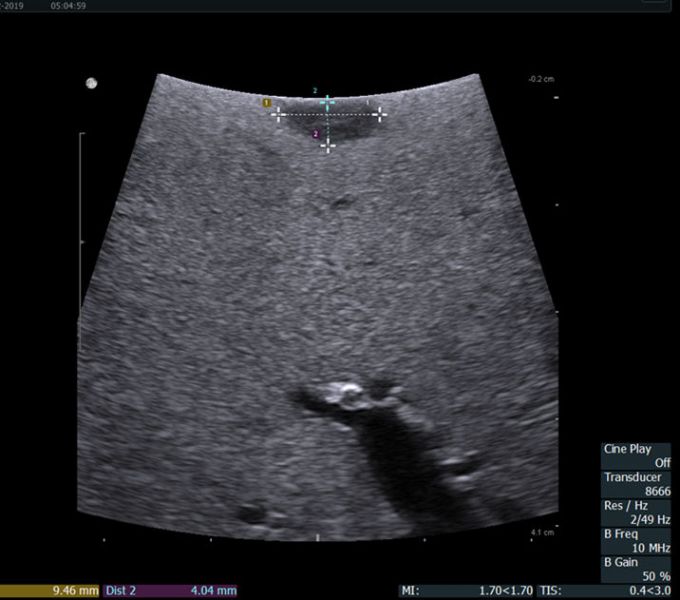

术中超声示肝IV段肿块大小及距肝表面距离